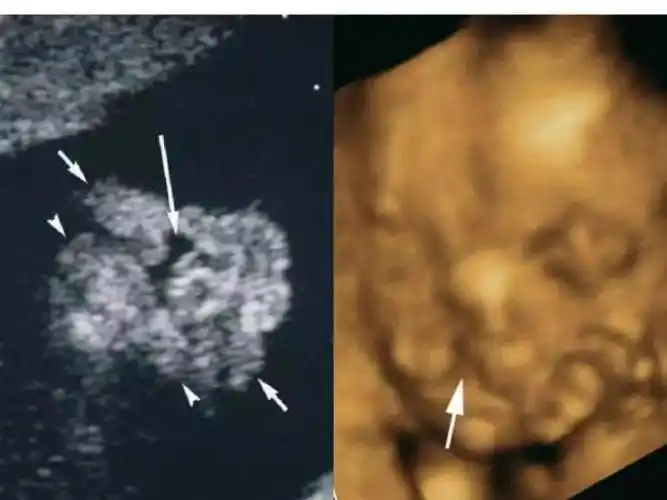

知多点 | 胎儿唇腭裂,你需要了解更多